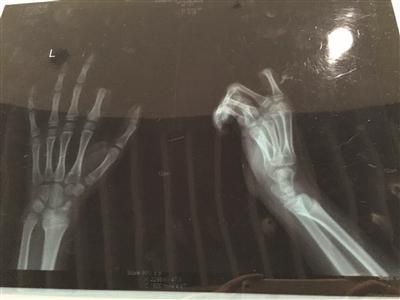

X光片显示孩子食指两个指节被切断

不一会儿,饭做好了,听见这段对话的邹某,已经对小朋一直玩游戏的状态有些不满,便忍不住对小朋训斥了几句。当时,小朋手里正拿着叉子在叉土豆泥吃,听了爸爸训斥的话后,立马就炸毛了,放下手中的叉子,转身就拿起了身后矮桌上的菜刀,朝着自己的左手切下去,当场,食指的两个指节就掉了下来。

手术历经3个多小时。若能顺利度过一个星期的危险期,接上去的手指便能成活。苏州大学附属瑞华医院手外科主任周荣是小朋的主刀医生。下午1点不到,小朋便被推进手术室做准备,下午4点左右,小朋才被推出了手术室,转入病房。不幸中的万幸,经过三个多小时的手术,小朋的手指被暂时接上。小朋的父母都没想到孩子会做出如此举动,看到手指掉下来了,都愣住了。随后,二人又立刻反应过来,将断指用纸包好,放进口袋,带着小朋便赶到了医院。